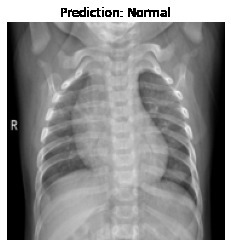

Currently, there is an urgent need for efficient tools to assess the diagnosis of COVID-19 patients. In this project, we propose a constructive solution for detecting and labeling infected tissues on CT lung images of such patients. To cut down false positives our model is trained on 4 types of lung CT images : COVID, Viral Pneumonia, Lung Opacity and normal images to get the best possible results with highest accuracy.

We built it using Tensorflow 2.x using Python. We have developed a Convolutional Neural Network model with an average accuracy of more than 85%.

We are proud that among the top 5 models, one of our models achieved 88.8% accuracy with very low loss.